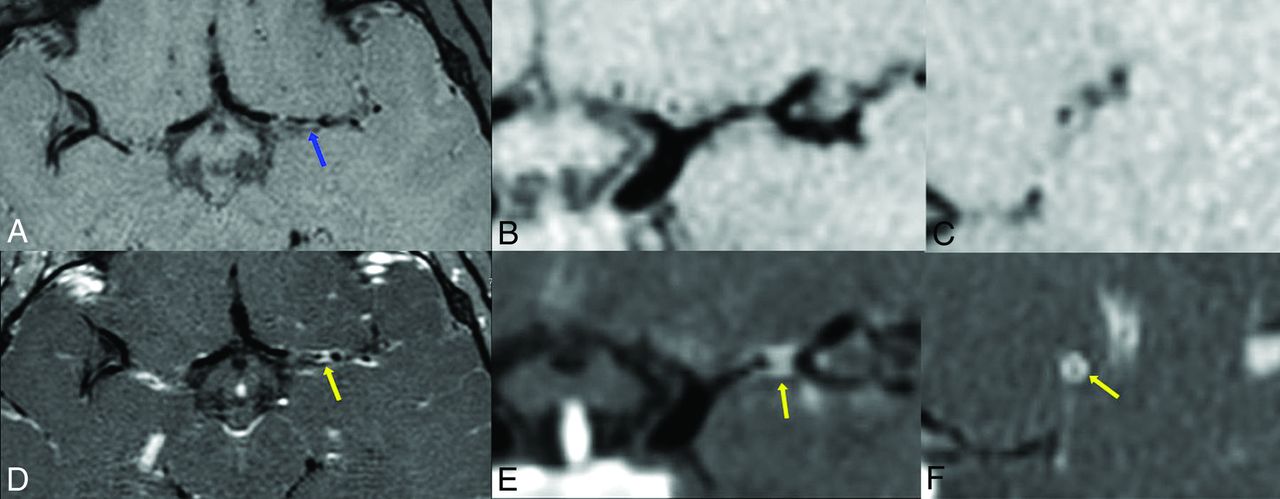

COVID-19-associated left MCA vascular territory acute infarcts in a pediatric patient. Axial diffusion (A), ADC map (B), and FLAIR (C) images demonstrate foci of restricted diffusion (blue arrows) and cytotoxic edema (yellow arrow) within the left middle cerebral artery vascular territory, consistent with acute infarcts. Anterior projection from a TOF-MRA of the head (D) demonstrates a focal segment of moderate stenosis within the left M1 middle cerebral artery (red arrow).